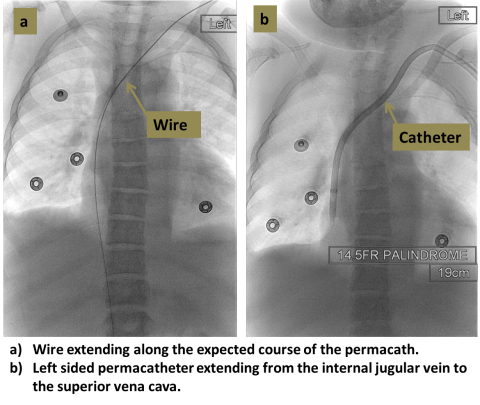

An interventional radiologist uses ultrasound to access the target vein, most commonly the internal jugular vein in the neck. X-rays are then used to guide placement of the catheter so that the tip lies in the central veins near the heart. The catheter is tunneled beneath the skin and exits the skin usually in the upper chest.